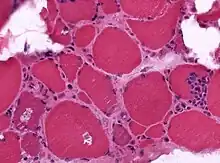

| A muscle biopsy from someone who is diagnosed with myositis. | |

Muscle biopsies are the most reliable tests for diagnosing myositis.[4]